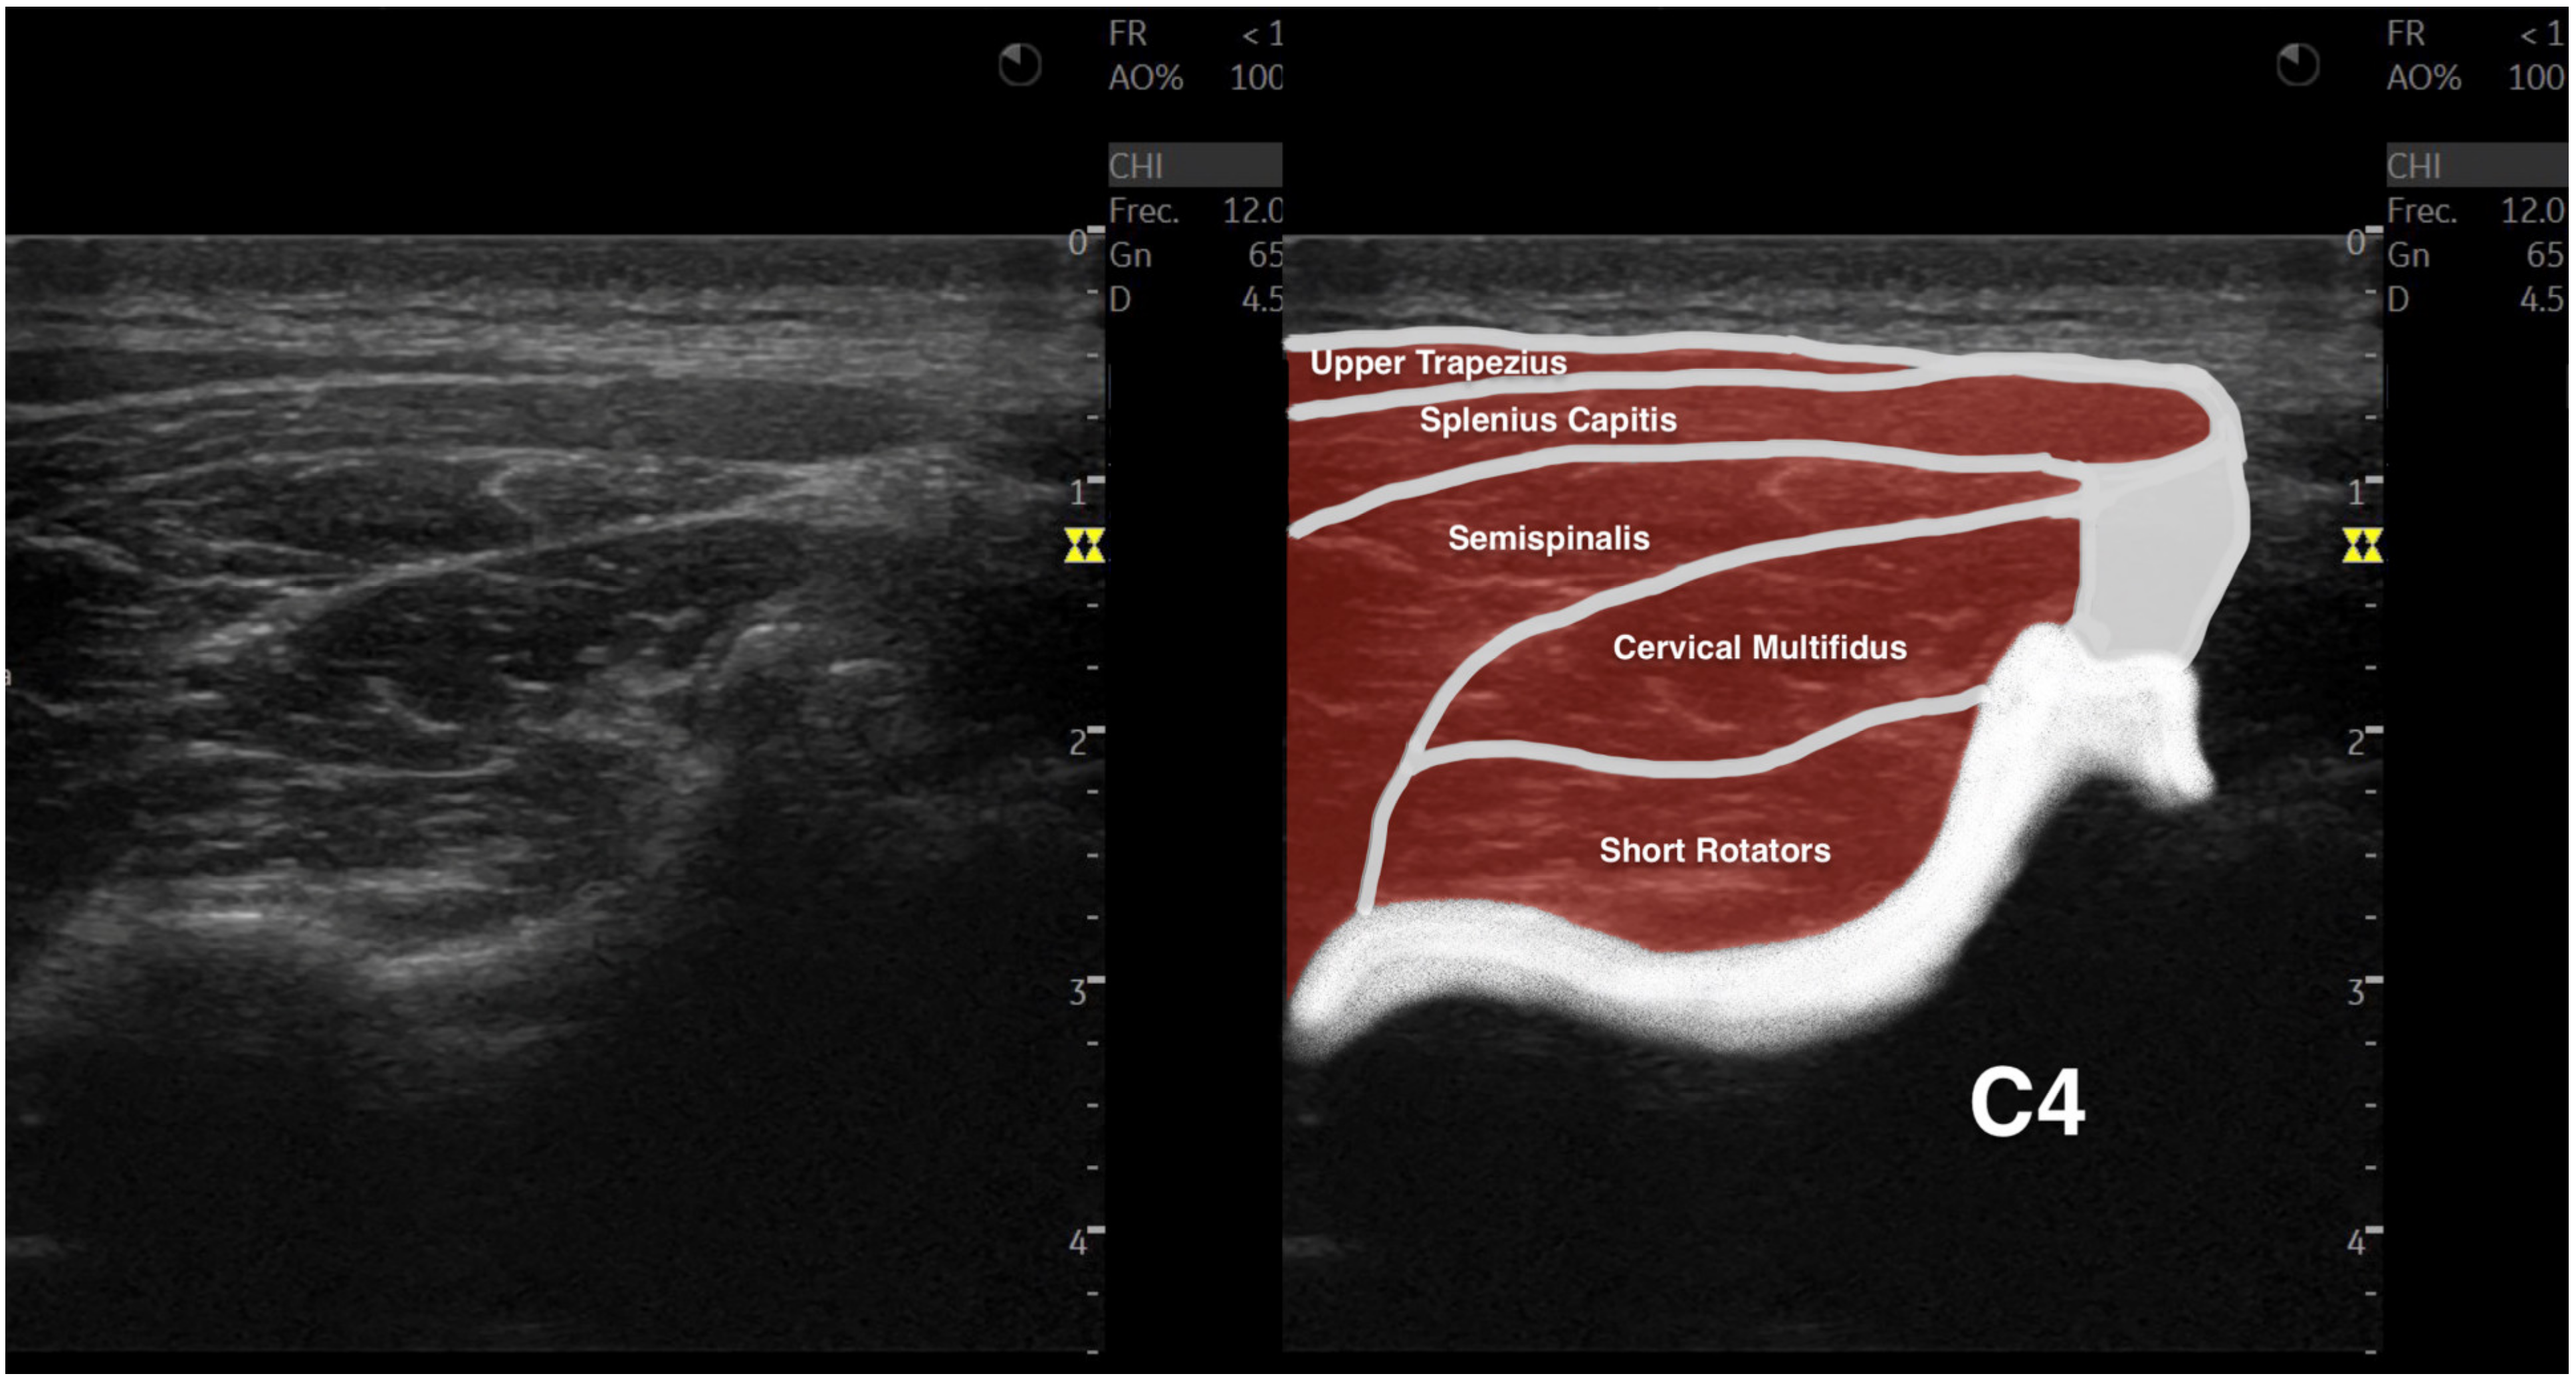

2.4.3. Ultrasound Imaging Acquisition

2.4.4. Measurement of Muscle Morphology and Quality